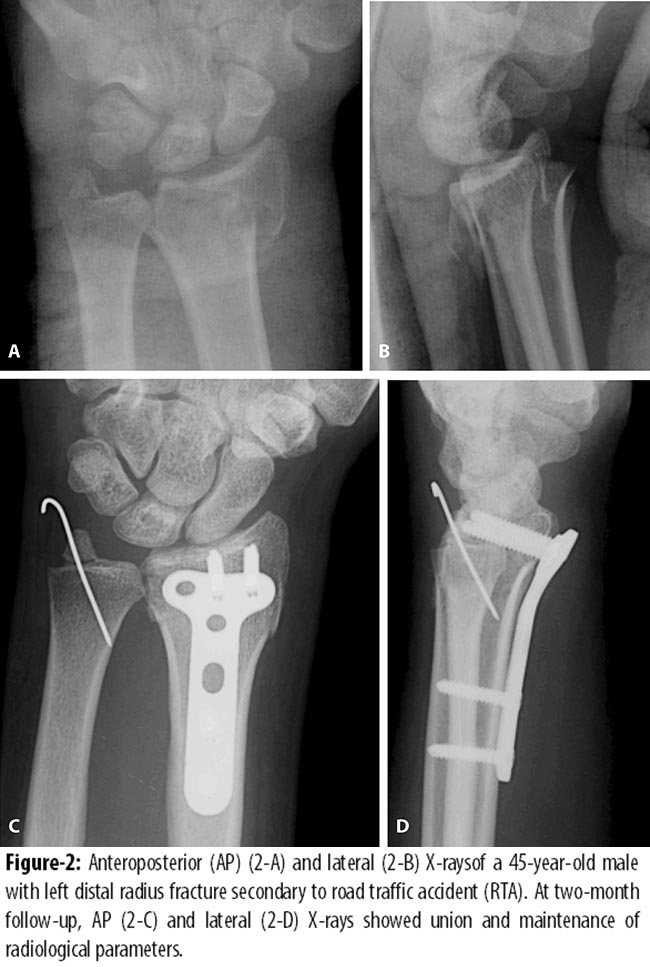

In our study, principle of angular stability was clinically applied by volar placement of locking plate for intra-articular distal radius fractures. Volar approach was preferred to facilitate reduction and plate fixation and to limit the risk of extensor tendon alteration. We evaluated the patients for the recovery of hand function and radiological parameters post fixation with LCP. Our results are consistent with earlier findings in terms of function of hand and radiological outcome.13-16 In most cases effective restoration of anatomic alignment was acquired and maintained (Table-2; Figures-1 and 2) regardless of the direction of fracture angulation.